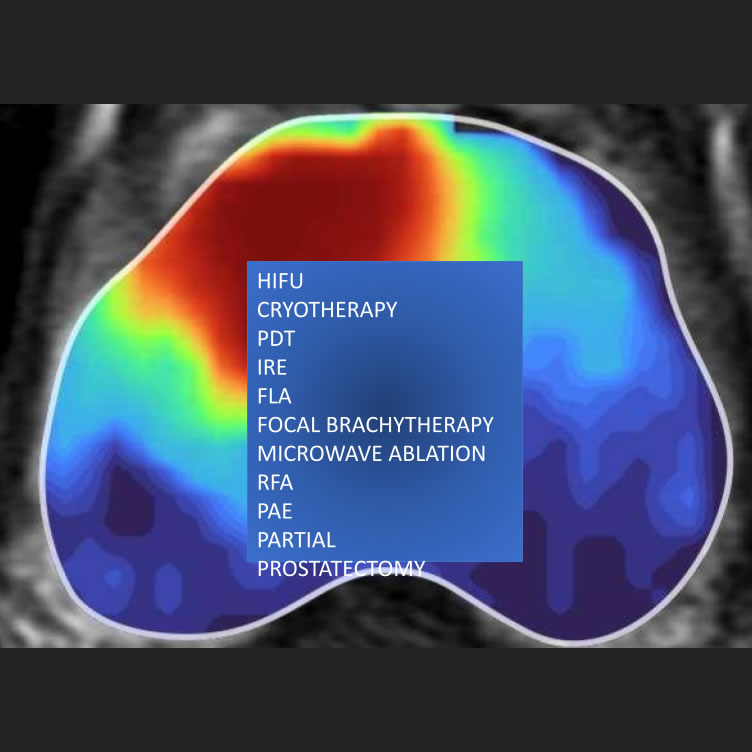

Il tumore della prostata è la più frequente neoplasia nell’uomo. Oggi, oltre alle più avanzate tecniche robotiche e i nuovi

trattamenti radianti, in grado di trattate l’intera ghiandola prostatica, sono emerse numerosi nuovi trattamenti miniinvasivi per

poter trattare solamente una piccola parte di prostata, preservando il resto dell’organo e la sua funzione. Il prof. Mauro Gacci è

stato inviato al prestigioso congresso internazionale IBUS (International British Urological Society) a parlare dei diversi

trattamenti focali di prostata.

Le terapie focali sono nuove tecniche che mirano a distruggere esclusivamente il tumore presente nella prostata, risparmiando i

tessuti sani circostanti. A differenza dei trattamenti tradizionali, che coinvolgono l’intera ghiandola prostatica, queste nuove

tecniche si concentrano su aree molto precise, nei casi in cui il tumore di prostata è localizzato. In questo modo, si limitano

significativamente gli effetti collaterali, come l’incontinenza urinaria e la disfunzione erettile, che spesso derivano dal

trattamento di tutta la prostata in blocco sia con chirurgia che con radioterapia

Come presentato durante il convegno dal Prof. Gacci, ad oggi esistono bel 10 differenti tecniche di terapia focale del tumore prostatico. In alcuni casi, come per la brachiterapia o l’HIFU, si tratta di tecniche che hanno raggiunto un discreto livello di validazione scientifica, mentre molte altre – supportate da pochi dati in letteratura - devono essere considerate ancora metodiche sperimentali. Solamente pazienti con tumori di prostata localizzati e poco aggressivi sono ad oggi candidabili a questo tipo di trattamento. Per tutti gli altri la chirurgia e la radioterapia -associate anche tra loro ed a nuove terapie farmacologiche –

rappresentano ancora i trattamenti di riferimento.

Uno studio che abbiamo appena pubblicato, in collaborazione con l’università di Hong Kong, ha permesso di valutare i risultati oncologici di oltre 8,000 pazienti affetti da tumore di prostata, trattati con diverse tecniche di terapia focale.

Nonostante la grande eterogeneità dei dati analizzati, dovuti alla disponibilità di ben 10 differenti tecniche di terapia focale, questo approccio innovativo sembra una nuova promettente opzione terapeutica per il tumore di prostata.